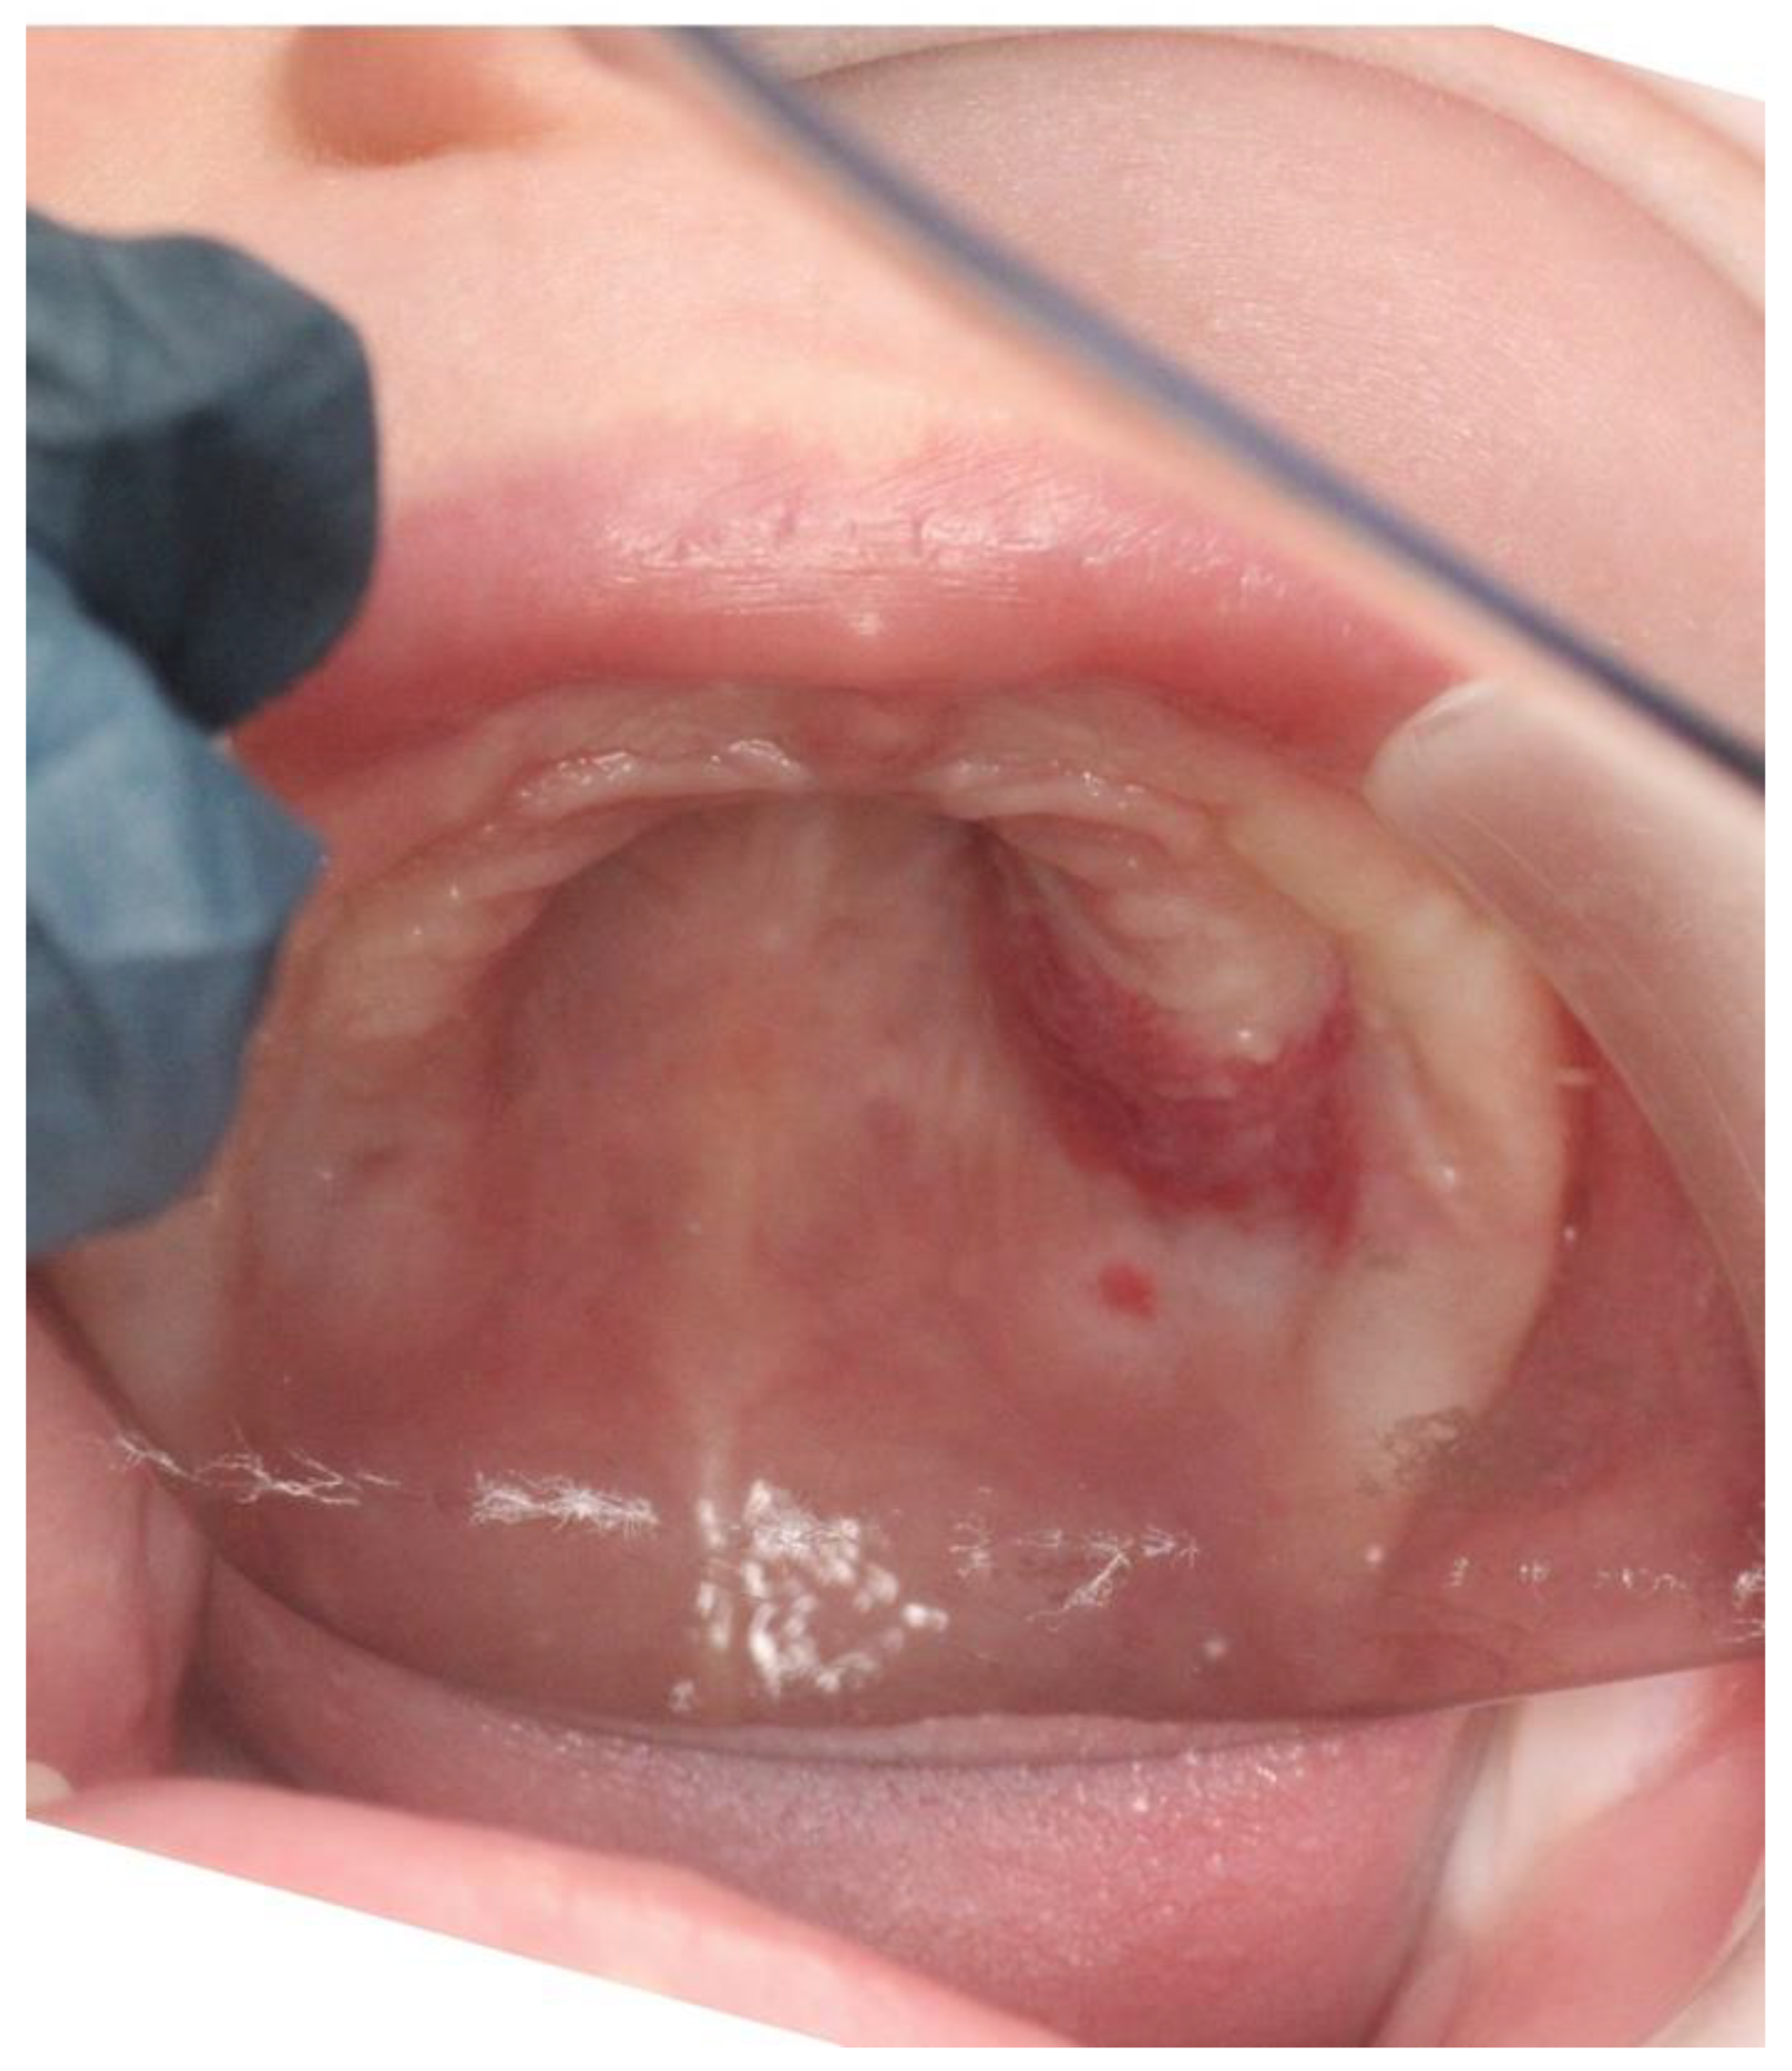

The intra-oral clinical exam showed (Figure 1 and Figure 2) a 2.5 cm × 3.5 cm well-circumscribed red/crimson macule with a 1 mm white dot in the center, located on the posterior portion of the upper left alveolar ridge spanning to the mid-palate. There were no other abnormal soft tissue findings. No radiographs were taken. A history from the parent revealed that the lesion had been present shortly after birth and had been growing since. The patient did not present with any extra-oral swelling or other oral pathology. At present, aged 11 months, the lesion has not changed size (Figure 3).

Figure 1. Intraoral photograph showing a 5-month-old Caucasian female with a 2.5 cm × 3.5 cm well-circumscribed, non-contiguous, red/crimson macule with a 1 mm white dot at the center. It is located on the posterior portion of the upper left alveolar ridge, spanning to the mid-palate.